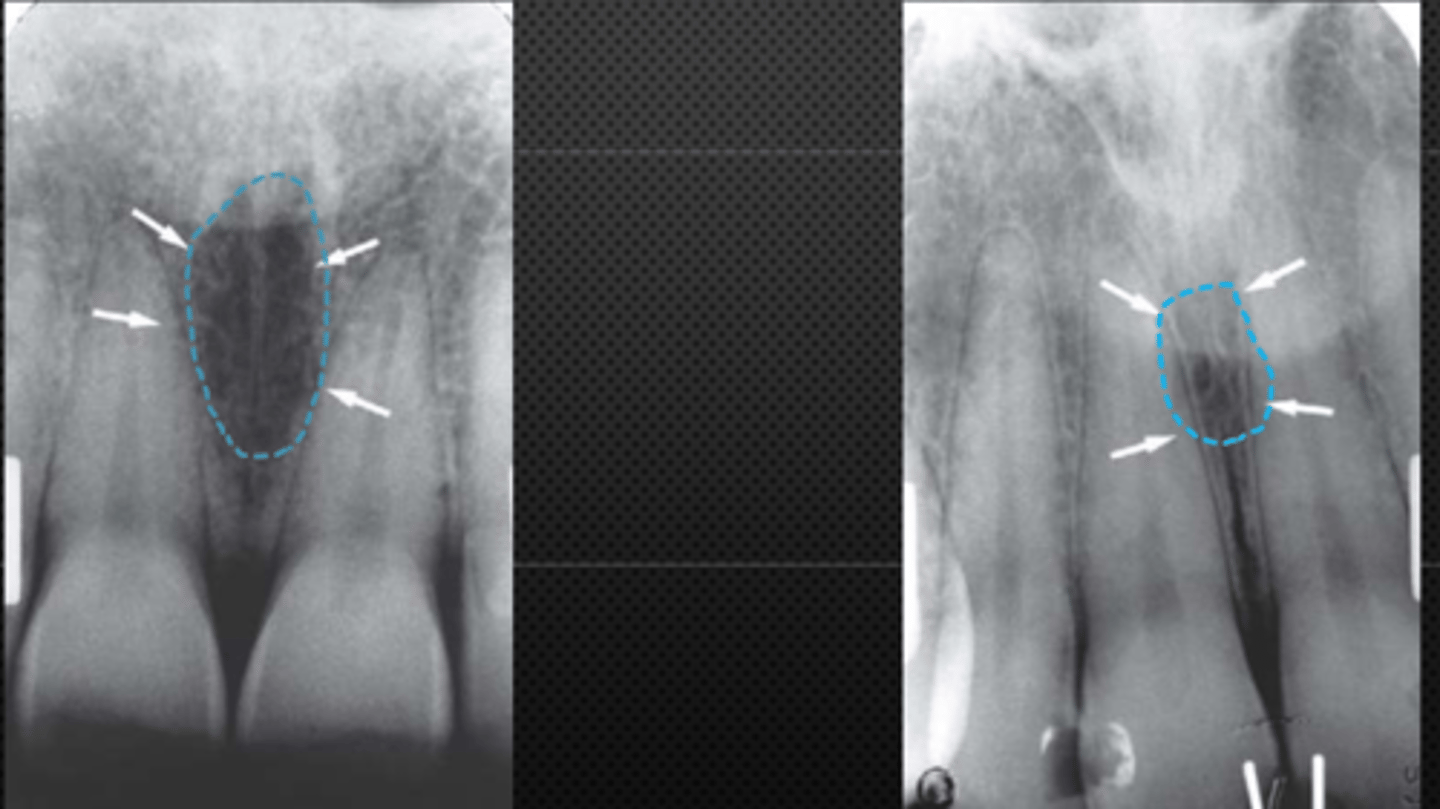

8

New cards

Nasopalatine canal

Identify the structure

<p>Identify the structure</p>

9

Superior foramina of the Nasopalatine canal